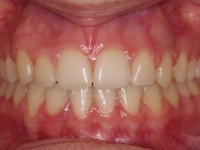

Clase II paciente 15 años

La paciente O.O. acude a nuestra consulta por:

– Canino 13 e incisivo lateral 42 en posición ectópica.

– Canino 23 incluido.

Con lo que decide realizarse un tratamiento de ortodoncia de duración de 24 meses con brackets damon Q.